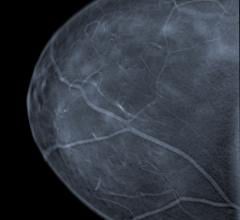

Mammography is a breast imaging technique that uses X-rays to diagnose and locate tumors of the breasts.